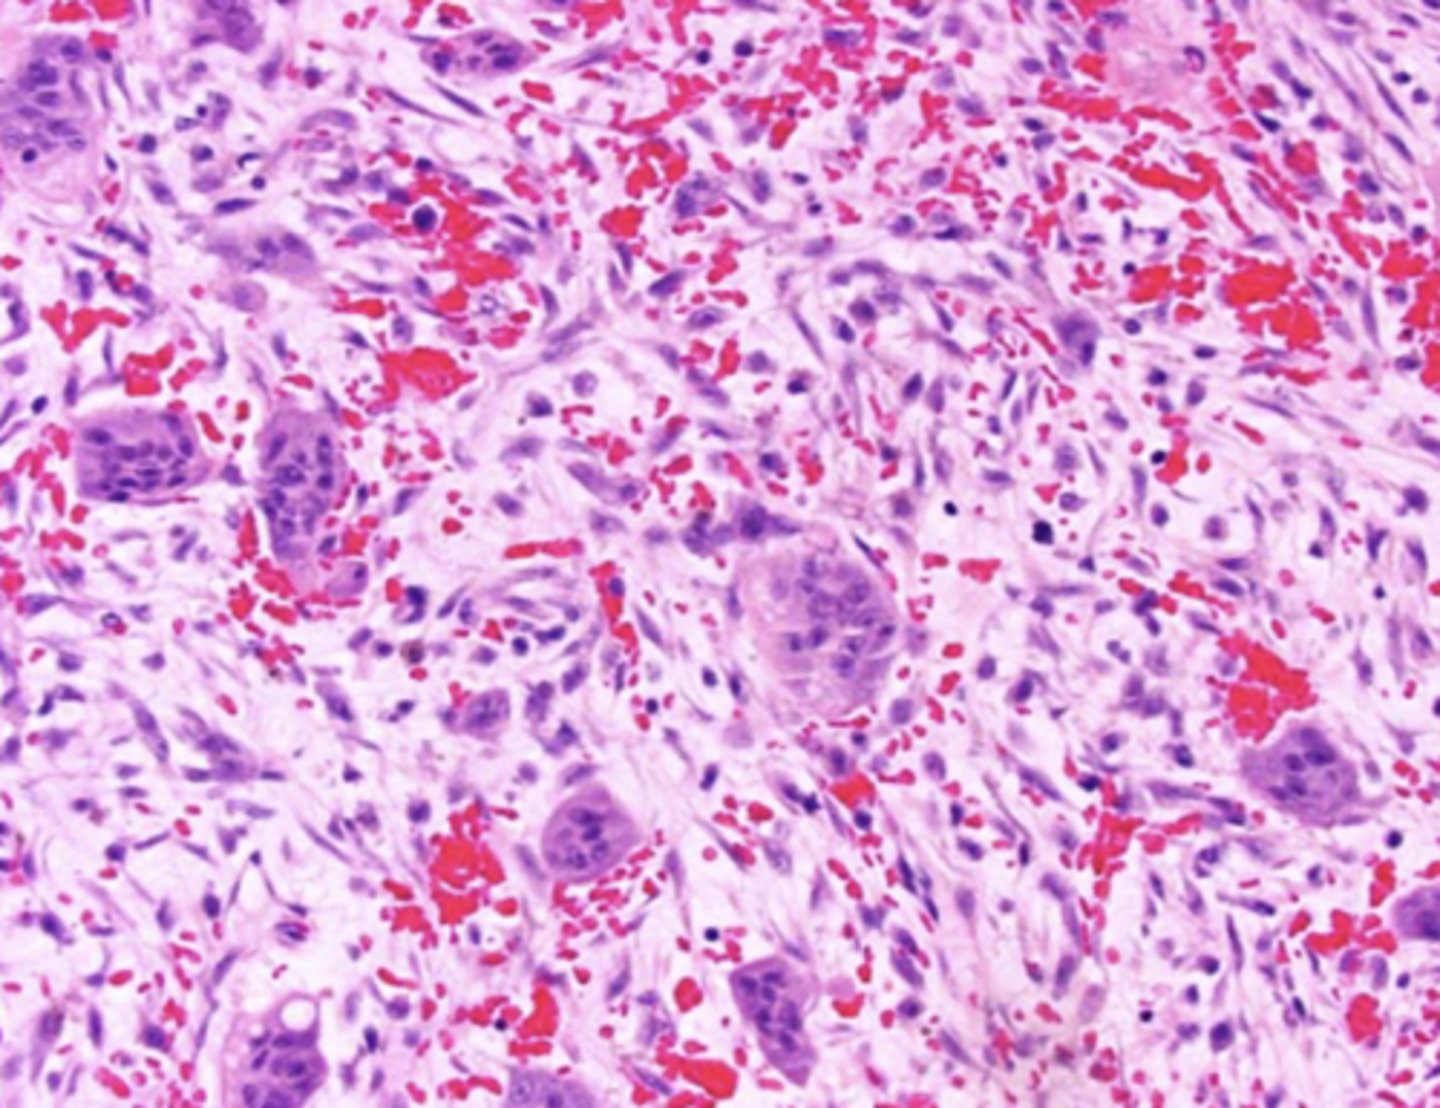

Central giant cell granuloma - histology

- Multinucleated giant cells

- Marcophages

- Areas of hemorrhage